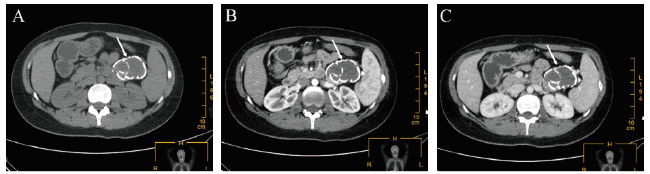

2021年3月10日行手辅助腹腔镜下胰尾联合脾切除术,具体手术步骤如下:①手辅助入路(图2A),上腹部正中切口,长约6 cm,切口处置入切口保护套,直视下离断胃结肠韧带,左肋下及左中腹处置入10 mm Trocar,以6.5号手套包裹切口保护套形成密闭装置,术者左手经过切口保护套进入腹腔,建立气腹;②探查胰尾处可见一大小约5 cm×5 cm肿物,表面光滑,质地较硬,活动较差;③于肠系膜上静脉左侧离断胰腺周围韧带和切开胰腺包膜;④离断脾动静脉和胰腺,断端水平交锁U式缝扎(图2 B、C);⑤离断脾周围韧带、取出标本(图2 D)。手术耗时135 min。

图2 一例SPN患者手辅助腹腔镜治疗术中图片

注:A为手辅助入路;B为捏持胰腺断端控制出血;C为直视下缝合胰腺断端;D为取出标本。